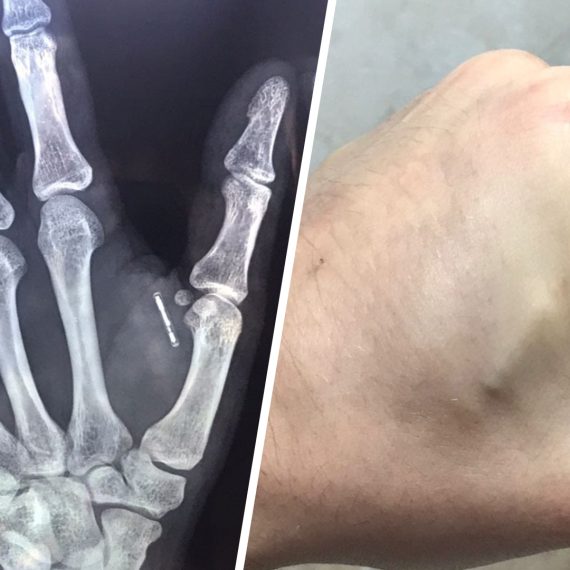

Маттиа Коффетти, 35-летний житель небольшого городка в провинции Брешиа,...